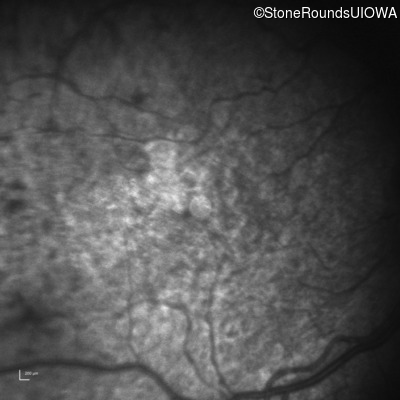

Infrared Fundus Photograph - Right - 20/1000 sc

Exemplar